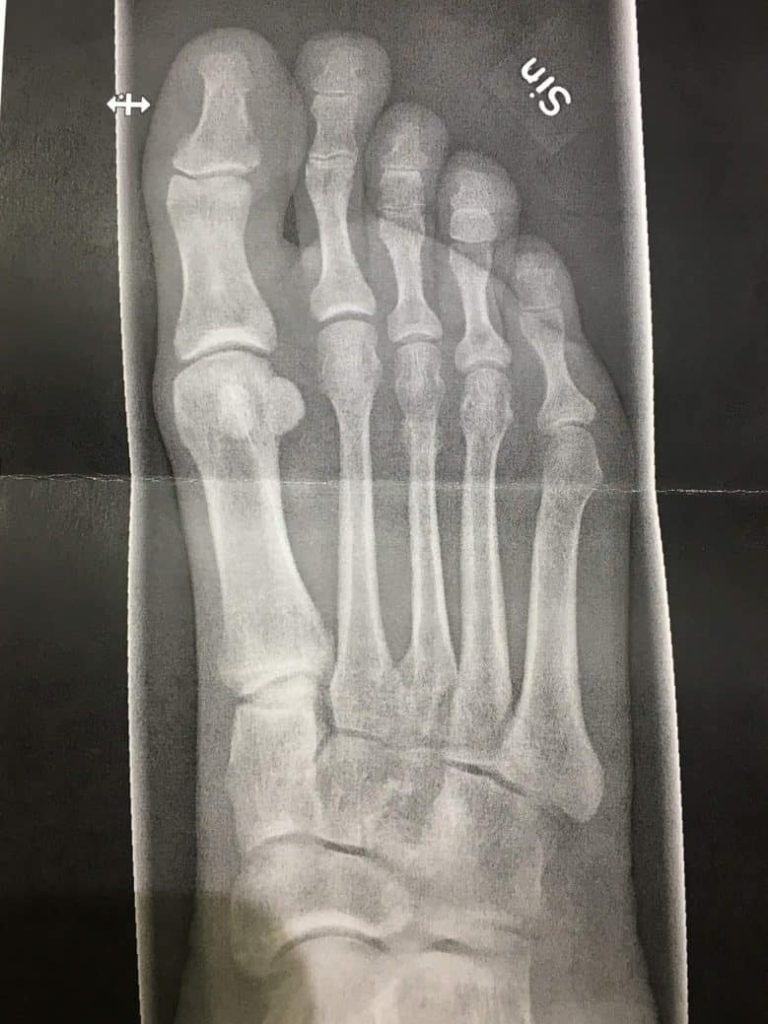

Så med dessa framsteg i bagaget hoppade jag återigen till röntgenavdelningen för vad jag hoppades skulle bli min tredje och sista gång. Vid det här laget ville jag förstås inget hellre än att plåtarna skulle visa på frakturen, vilket i så fall skulle tala om att läkningen var i full gång. Det som röntgenläkaren letar efter kallas för kallus, vilket refererar till den broskliknande vävnad som bildas där en fraktur uppstått när benet är under läkning. Så småningom kommer detta att lösas upp och det hela, rena benet är det enda som återstår. När kallus syns på röntgen innebär det att läkningen kommit långt, men också att en liten bit återstår. Medan jag låg på britsen i röntgensalen råkade jag höra brottstycken av konversationen inne på “kontoret” där de satt och analyserade plåtarna. “Råkade” är givetvis en sanning med modifikation – jag har nog aldrig spetsat mina öron så som jag gjorde då. Hur som helst så tyckte jag mig höra både “kallus” och “tredje metatarsalbenet” och mina förhoppningar sköt omedelbart rakt upp i skyn. Kunde det här vara sant? Kunde det här vara dagen som jag så ivrigt väntat på? Ja, det kunde det – när jag en timme eller så senare träffade ortopeden igen så var jag nära att hoppa upp i hennes famn och ge henne en kyss, eftersom hon i sin hand hade en kopia på röntgenplåten som visade världens snyggaste om än klart suddiga kallus. Efter nio veckors väntande fick jag äntligen min diagnos! Jag trodde aldrig att det skulle göra mig lycklig att få höra en läkare säga “stressfraktur på tredje metatarsalbenet”, men nog fasen gjorde det det. Läkaren rådde mig att pensionera ortosen men att se till att använda stadiga skor de närmaste veckorna, samt avvakta med löpning tills det nya året som en försiktighetsåtgärd. Spinningen var fritt fram att fräsa på med hur hårt jag ville, och egentligen gav hon grönt ljus till allt som inte orsakade direkt smärta. Det här var en sådan lyckans dag för mig, och jag log med hela ansiktet när jag gick ut till Mike i väntrummet, viftandes med röntgenbilden. Jag kunde äntligen se slutet på allting.